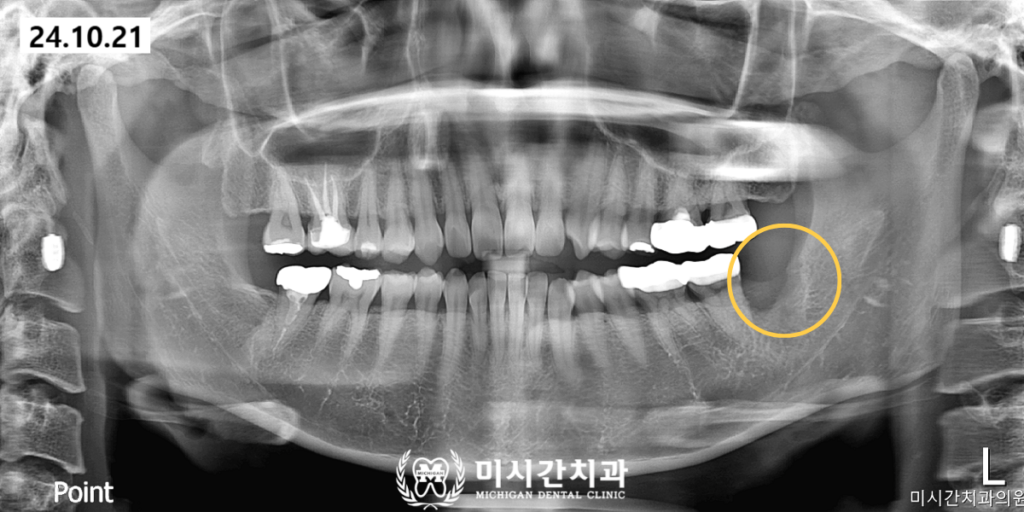

전체 수술 시간은 예상보다 짧게 소요되었으며

환자분은 발치 직후부터 우려했던 것보다

훨씬 편안한 상태를 유지하셨습니다.

수술 후 관리 단계에서도 미시간치과의

세심한 지침이 이어졌습니다.

발치 부위의 지혈을 돕고 빠른 회복을

유도하기 위해 주의사항을 상세히 안내해 드렸으며

소독과 실밥 제거를 위한 내원 일정까지

체계적으로 관리해 드렸습니다.

일주일 뒤 실밥을 제거하러 내원하셨을 때

환자분은 이전의 붓기와 통증이

말끔히 사라졌으며 씹는 기능 또한

정상적으로 회복되었다며

큰 만족감을 나타내셨습니다.